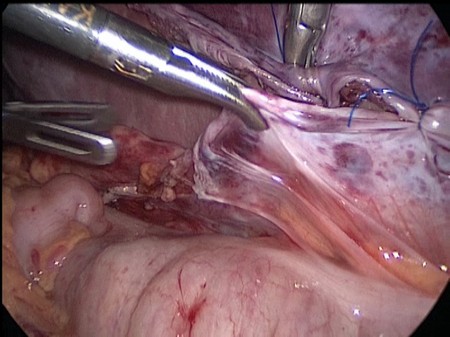

Листки брюшины сшиты над селезенкой отдельными узловыми экстракорпоральными швами нитями пролен 4-0 (Рис. 3).

Рис 3. Интраоперационное фото. Листки париетальной брюшины сшиты над селезенкой отдельными узловыми швами

Для профилактики сдавления селезеночных сосудов листок брюшины над сосудистой ножкой поперечно рассечен.

Гемостаз среза культи аргоновой и монополярной коагуляцией. Аппарат с сосудистой ножки снят, кровоснабжение культи селезенки восстановилось. Дополнительная деторсия селезенки на один оборот. Продольно рассечен листок брюшины по левому боковому каналу, листки брюшины мобилизованы. В созданный в забрюшинном пространстве карман уложена резецированная селезенка. Листки брюшины сшиты над селезенкой отдельными узловыми экстракорпоральными швами нитями пролен 4-0 (Рис. 3). Резецированный фрагмент селезенки удален из брюшной полости в эндопакете. Дренирование брюшной полости однопросветным страховым дренажем.